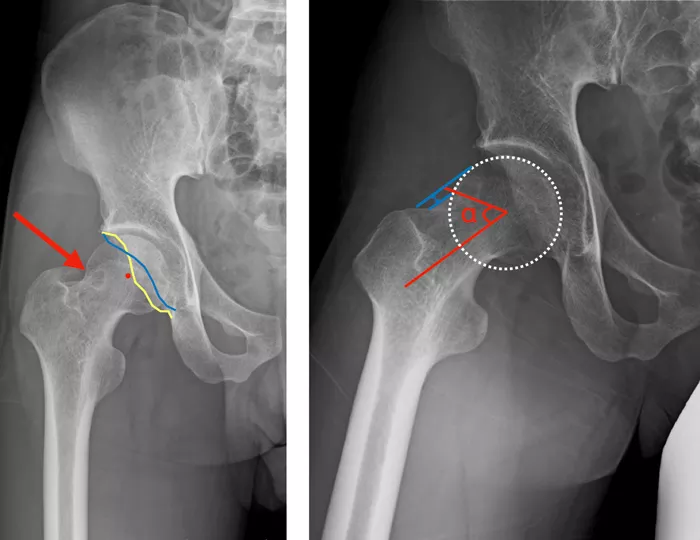

股関節X線正面像では寛骨臼形成不全および関節裂隙狭小化は認めず、寛骨臼にはcross over sign、posterior wall signを認め、大腿骨頭頚部移行部に骨皮質下透亮像を認めた(写真2左)。

Dunn viewではα角増大と大腿骨頭頚部移行部の肥厚を認め、Head-neck offset ratioの減少を認めた(写真2右)。

写真2

左 骨皮質下透亮像(赤矢印)、寛骨臼前壁(青)と後壁(黄)が交差するcross-over sign陽性で寛骨臼後捻が示唆される、骨頭中心(赤点)は寛骨臼後壁(黄)よりも外側でposterior wall sign陽性で後方の被覆不全が示唆される。

右 骨頭中心と頚部最狭部を結ぶ線と前方骨頭頚部移行部の曲率変化点と骨頭中心を結部線からなるα角の増大あり。骨頭と頚部のオフセット(青矢印)の減少を認める。